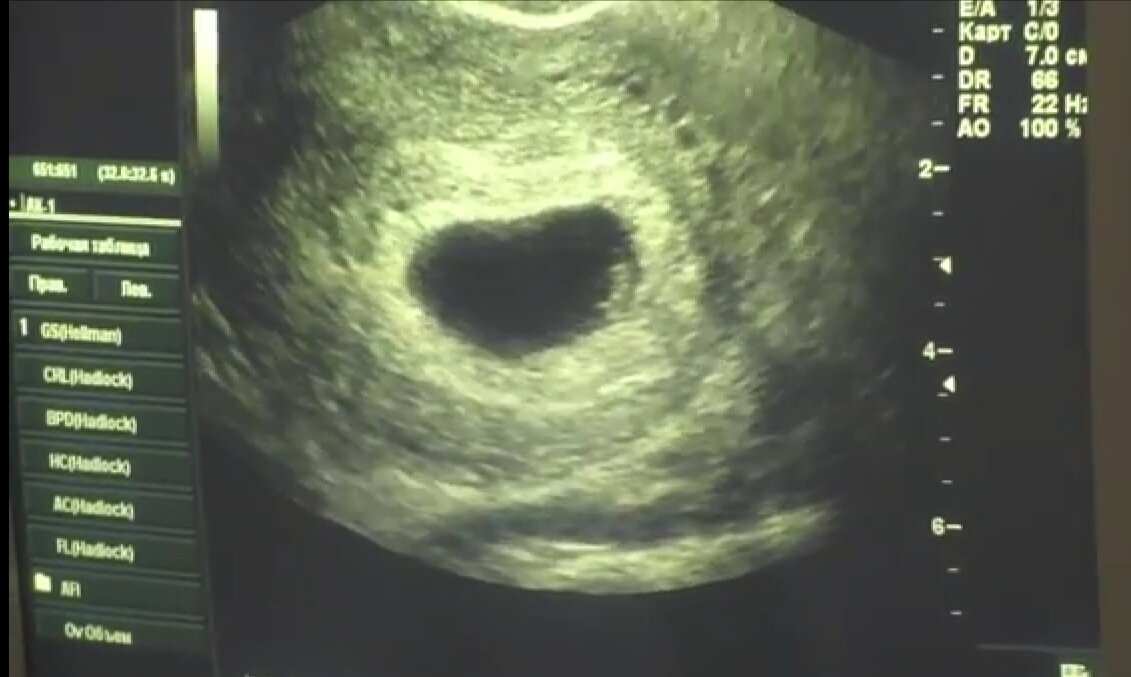

Вот тут начинается самое интересное. На этом УЗИ все с Таниным малышом хорошо! Даже сердечко послушали! Таня опять в шоке - кому верить и что это вообще такое? Хгч сдала уже два раза - все растет и удваивается. Цифры очень впечатляющие! Почему я злюсь? Понятно! Вот так наша бесплатная медицина отправила человека на медикаментозный аборт и могла лишить не только счастья, но и морально покалечить!